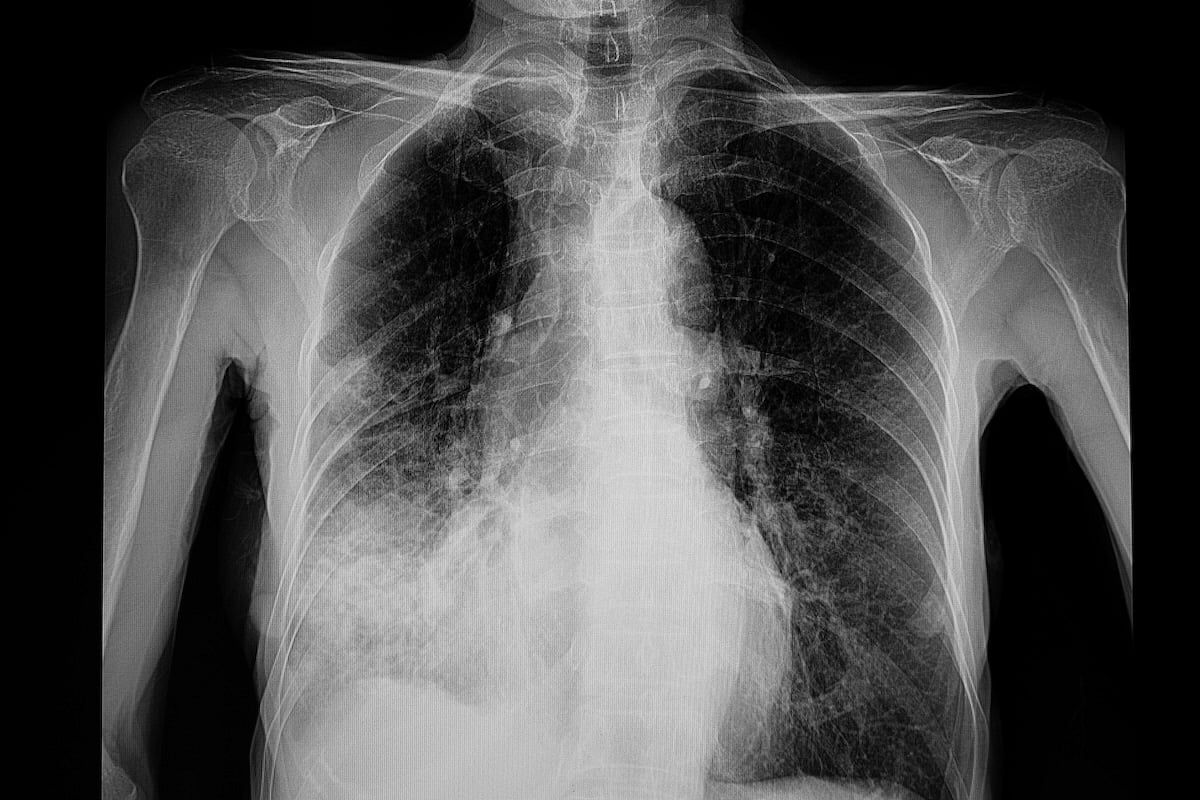

But there are two other types: Septicemic plague, which spreads throughout the body, and pneumonic plague, which infects the lungs.

Pneumonic plague, which caused the Arizona death, is also the easiest to spread, AP said.